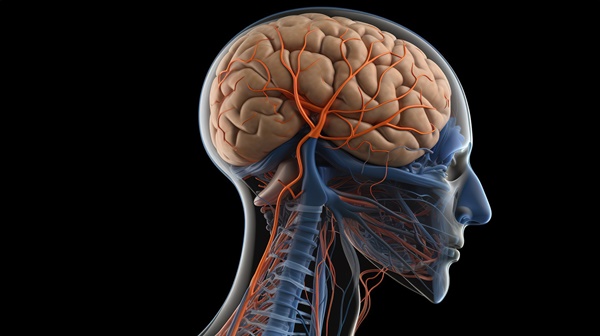

뇌종양 증상초기증상

뇌종양의 초기 증상은 종양의 위치에 따라 정말 다양하게 나타납니다. 뇌종양 초기증상 전두엽이라면 성격이 달라지거나 충동 조절이 어려워지고, 측두엽일 경우 말소리를 잘 이해하지 못하거나 헛소리를 하기도 해요. 후두엽에 생기면 시야가 좁아지거나 사물이 겹쳐 보이기도 합니다. 팔이나 다리에 힘이 빠지는 증상도 흔한데, 이는 운동신경이 있는 부위가 눌릴 때 나타나는 현상입니다. 어떤 분은 운전 중에 자꾸 실수를 반복하다 이상함을 느껴 병원에 갔다가 뇌종양을 발견했다고 해요. 그만큼 익숙한 행동 속에서 달라진 패턴을 알아채는 게 중요합니다.